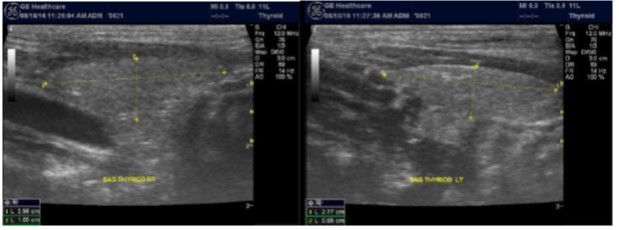

The superficial location of the thyroid gland renders it ideal for ultrasound examination 8. High resolution grey scale images can easily be obtained using high frequency transducer. In the transverse view, normal thyroid gland has the butter fly appearance, with left and right lobes connected with a narrow isthmus, Figure 1A. Both lobes can be imaged separately in the longitudinal plan, Figure 1B

Figure 1A.Normal thyroid gland transverse view

Normal thyroid gland transverse view

Figure 1B.Normal thyroid gland long view

Normal thyroid gland long view